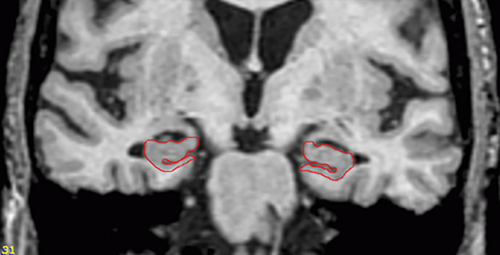

Un nuovo studio pubblicato oggi online su Neurology dimostra che la mancanza di restringimento nella zona del cervello chiamata ippocampo può essere un segno che le persone con problemi di pensiero e di memoria possono avere la demenza a Corpi di Lewy, piuttosto che l'Alzheimer. L'atrofia dell'ippocampo, l'area del cervello responsabile del pensiero e della memoria, è un segno precoce di Alzheimer.

Nello studio sono state eseguite scansioni MRI cerebrali a 160 persone con decadimento cognitivo lieve, per misurare le dimensioni dell'ippocampo. Hanno anche eseguito test annuali per una media di due anni. Durante questo periodo, 61 persone (38%) hanno sviluppato l'Alzheimer, e 20 persone (13%) sono progrediti alla probabile demenza con Corpi di Lewy. Poiché la malattia dei Corpi di Lewy può essere diagnosticata solo da una autopsia dopo la morte, si parla di «probabile demenza a Corpi di Lewy». I ricercatori fanno notare che i loro risultati devono essere confermati da studi che usano le autopsie per la diagnosi finale.

Le persone senza restringimento dell'ippocampo avevano una probabilità 5,8 volte maggiore di sviluppare una probabile demenza da Corpi di Lewy rispetto a quelli che avevano l'atrofia ippocampale. Diciassette delle 20 (85%) persone che hanno sviluppato la demenza da Corpi di Lewy avevano un volume di ippocampo normale; al contrario 37 delle 61 (61%) che hanno sviluppato l'Alzheimer avevano atrofia dell'ippocampo.